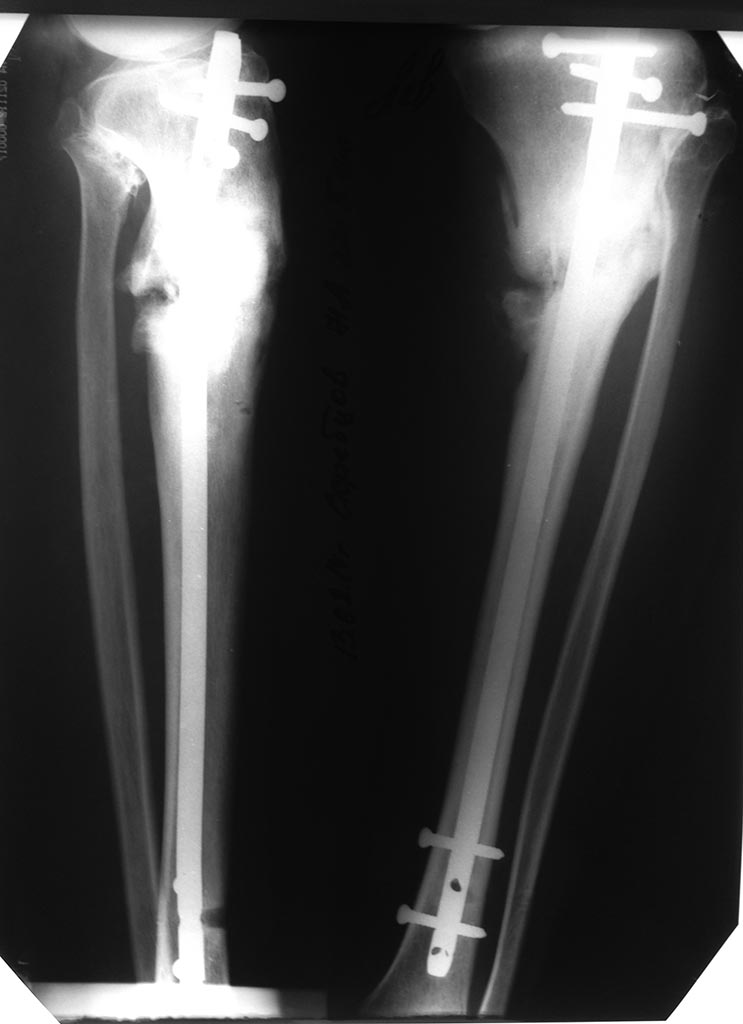

Добрый вечер коллеги. В нашу клинику обратился пациент с очень

интересным клиническим наблюдением. И так.... Пациент юноша, 22 года. В

2013 году травма в результате падения с мотоцикла, получил открытый

перелом верхней трети левой большеберцовой кости. Первая

помощь оказана по месту травмы. Произведено ПХО ран и наложение аппарата

внешней фиксации на левую нижнюю конечность.

Раны зажили и было принято решение продолжения

лечения в аппарате. Фиксация в аппарате 6 мес. Со слов пациента

проводились периодический перемонтаж аппарата перепроведение спиц, так

же со слов в области проведения спиц воспалительные явления с локальными

признаками нагноения. Через 6 месяцев аппарат

демонтирован, при осевой нагрузке пациент отметил искривление левой

голени и патологическую подвижность. на контрольных Ро выявлен

псевдоартроз верхней трети большеберцовой кости. Выполнен остеосинтез

штифтом с блокированием.

Через 4 мес. пациент обратился в нашу клинику с жалобами на боли в

области левого коленного и голеностопного суставов. На МСКТ левой голени

диагностирован сформировавшийся ложный сустав верхней трети левой

большеберцовой кости.

Учитывая данную клиническую и Ро картину сомнений в том

что надо переделать нет, но мучает извечный вопрос, как и чем?

операций. И мы больше склоняемся к идее перештифтовать с

рассверливанием, но есть вопрос с точкой доступа. Но может коллеги

предложат другие варианты? Заранее спасибо.